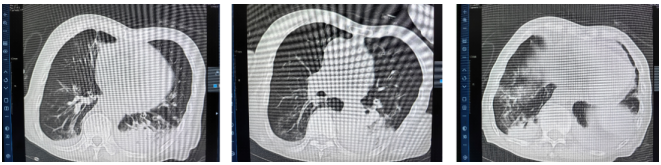

12月22日胸部CT:双肺多发肺大疱,双肺散在实变,右肺中叶内侧段节段性肺不张并支气管扩张,双肺支气管管壁增厚,管腔狭窄,左右主支气管、双肺支气管内痰栓形成,双侧胸膜增厚。

12月26日胸部CT:与12月22日相比,双肺实变较前增多,新增双侧胸腔少量积液图1。颅脑CT:右侧半卵圆中心腔隙灶,脑白质疏松,脑萎缩。血气分析pH 7.42,PaO2 93 mmHg,PaCO2 42 mmHg,HCO3- 26.8 mmol/L,P/F 265.7 mmHg(经鼻高流量氧疗)。

图1  胸部CT上图:2022-12-22,下图:2022-12-26